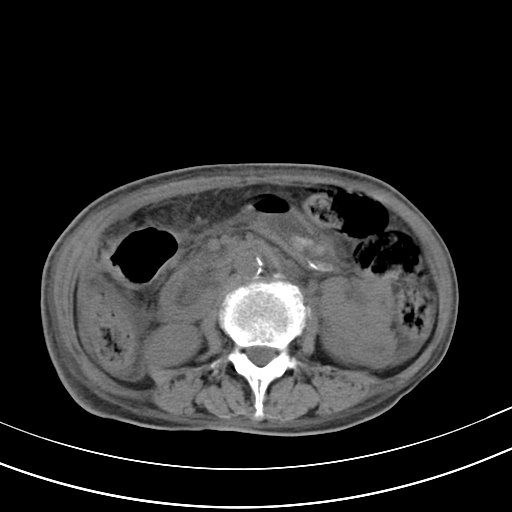

病人上腹部胀痛拌全身黄染八天

肝内胆管及胰管扩张,胰头增大考虑为胰头区占位,肝门淋巴结增多,考虑为转移。建议增强,脾大,胆囊大,壁厚,慢性胆囊炎。胃壁好像也增厚,且有一肿物。

胆囊增大,肝管扩张

脾大,

腹水,右胸腔少量积液。

胰腺炎。

1)考虑胰头癌并胆系低位梗阻;建议行ct增强扫描检查。2)慢性胆囊炎。3)脾大。4)少量腹水。5)双侧少量胸腔积液。